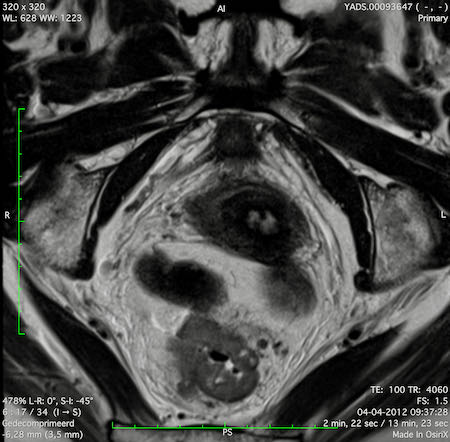

Hình ảnh

Các hình ảnh được cung cấp cho thấy ung thư biểu mô tế bào nhẫn với tình trạng dày lan tỏa thành trực tràng, hình ảnh bia bắn điển hình, và sự xâm lấn mỡ mạc treo trực tràng.